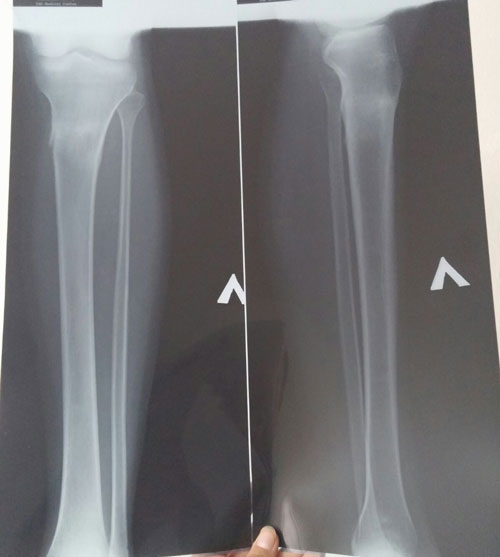

Рентген контроль в 1,5 месяца.

Здравствуйте, Карамелька! сращение железное, монолит! Ножки супер красивые, ещё раз напросились на комплимент!